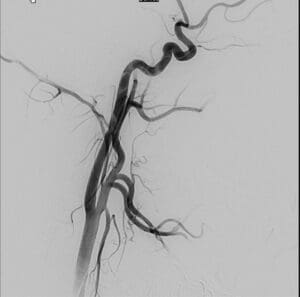

צוות מצנתרים בראשות ד"ר ולדימיר בורודצקי, מצנתר מוח בכיר ביחידה, ביצעו צנתור מוח מורכב בהרדמה מלאה שארך מעל ארבע שעות.

במהלך הצנתור המורכב התברר כי עורק התרדמה הפנימי משמאל חסום ממוצאו. החסימה הייתה עקשנית ולא ניתנת לפתיחה בדרכים המקובלות בצנתורי שבץ. לבסוף הוחלט על השתלת תומכן (סטנט) באיזור החסימה בעורק במוח, מה שאפשר הוצאת חלקי קרישי דם ופתיחת החסימה.

הצנתור המורכב עבר בהצלחה, כאשר כבר בחדר הצנתור מצבה של ש' השתפר והיא הצליחה להזיז את הרגל והיד והשתפרה משמעותית בדיבור. לאחר הצנתור ש' הועברה הועברה לטיפול ביחידה לטיפול נמרץ ילדים.